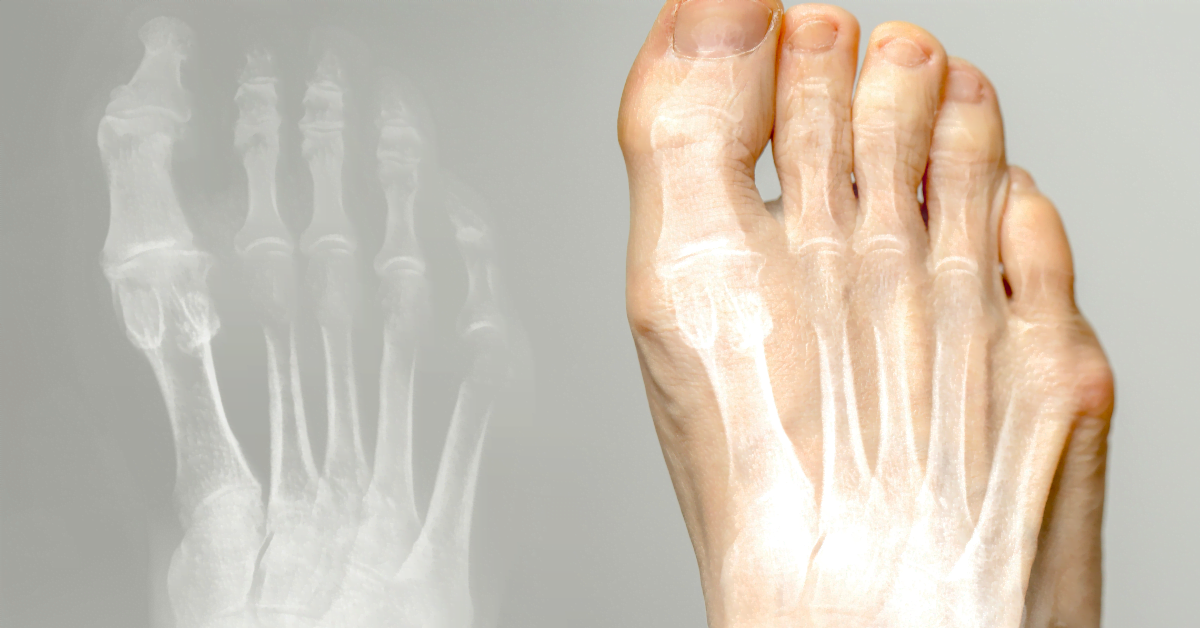

Qu’est-ce que l’hallux valgus ?

L’hallux valgus est une affection dans laquelle le gros orteil se plie vers les autres orteils et forme une bosse ou « bosse du pied » à la base du gros orteil. Il s’agit d’un type de pied valgus, c’est-à-dire d’une position déviée du pied.

Symptômes de l’hallux valgus

L’hallux valgus peut présenter différents symptômes, en fonction du degré d’avancement de la maladie. Les symptômes les plus courants sont les suivants

- Une grosseur à la base du gros orteil.

- Douleur au niveau du tubercule du pied, en particulier lorsque vous portez des chaussures.

- Rougeur et gonflement autour de la masse du pied.

- Sensation de brûlure ou d’inconfort dans le pied.

- Difficulté à marcher.